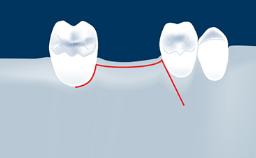

Complications of Sinus Floor Elevation

Sinus floor elevation using either the lateral window or transcrestal approach is a predictable surgical procedure with proven success, low complication rates, and high survival rates.

However, as with all surgical procedures, complications and failures do occur.

This learning module will provide an overview of the most commonly seen intraoperative and postoperative complications associated with sinus floor elevation and will discuss management in terms of preventative measures as well as treatment strategies.